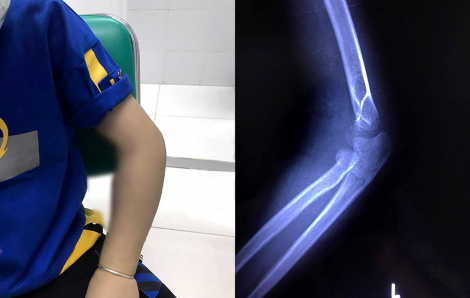

Continue reading »Kiêng cữ đầu năm, nhiều người bệnh trở nặng mới đi cấp cứu

PNO – Sợ xui xẻo khi đến bệnh viện ngày đầu năm, nhiều người ráng chịu đựng. Qua tết, mới chịu vào viện thì bệnh đã trở nặng. Sản phụ ở TPHCM mang song thai, sinh một bé ở nhà, một bé ở bệnh viện Nam thanh niên nhập viện vì mở bình rượu bằng